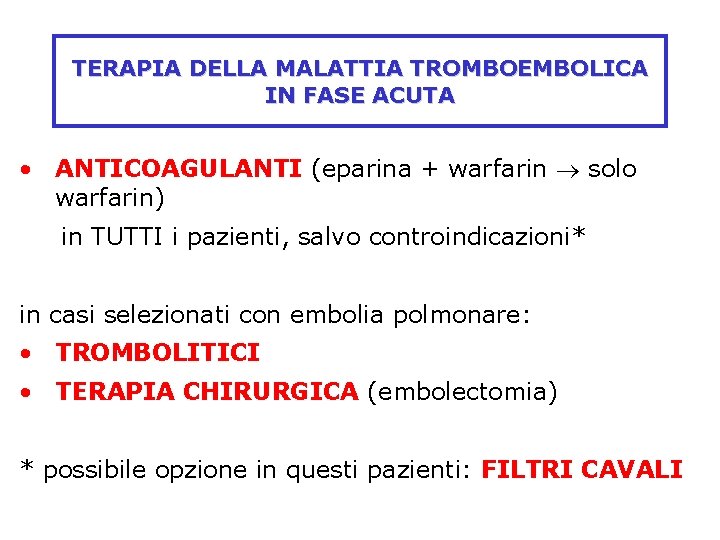

TERAPIA DELLA MALATTIA TROMBOEMBOLICA IN FASE ACUTA • ANTICOAGULANTI (eparina + warfarin solo warfarin) in TUTTI i pazienti, salvo controindicazioni* in casi selezionati con embolia polmonare: • TROMBOLITICI • TERAPIA CHIRURGICA (embolectomia) * possibile opzione in questi pazienti: FILTRI CAVALI